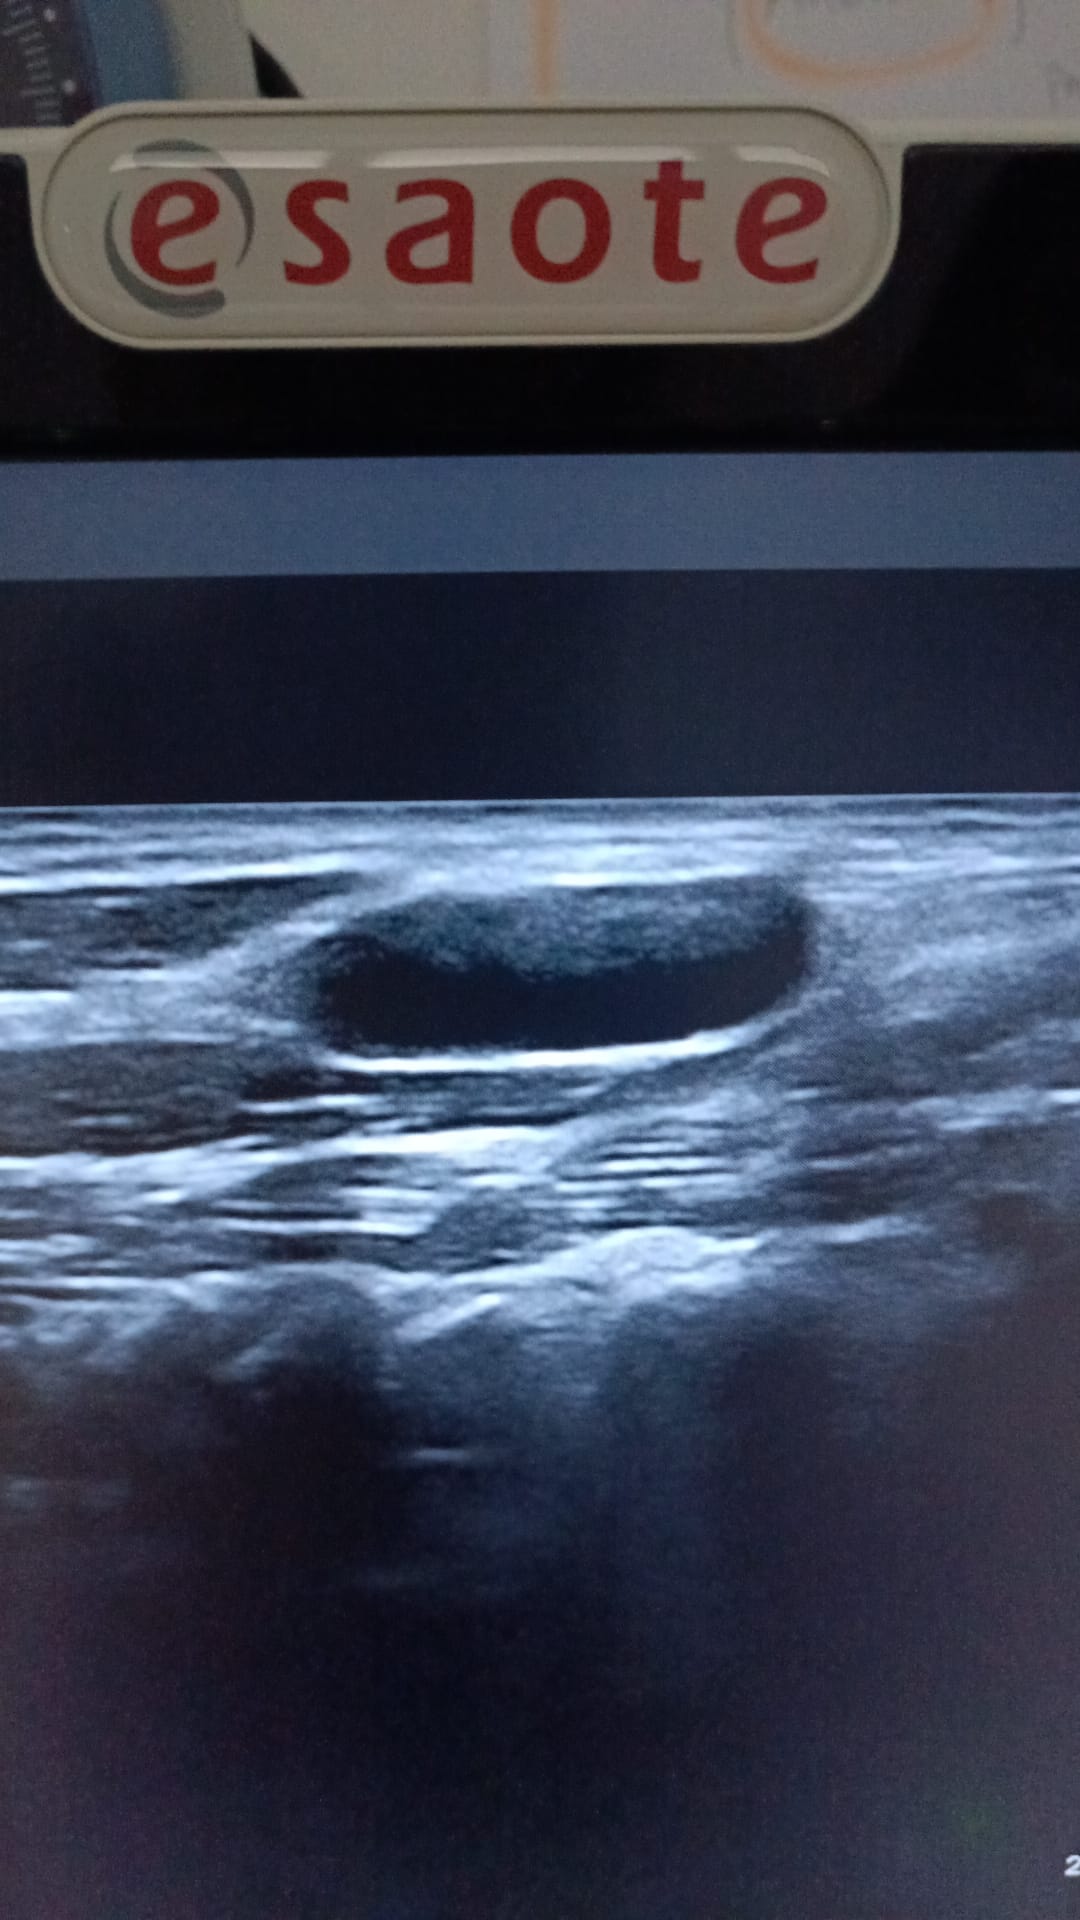

Se le realiza una Ecografía clínica a pie de cama (POCUS), donde se observan múltiples adenopatías anecoicas en ambas cadenas submandibulares y laterocervicales, algunas de 3 cm aproximadamente, de aspecto redondeado y con sugestiva presencia de hilio.

En LTI, se observa nódulo espongiforme en su parte superior sólido con calcificaciones en región inferior de más de 2 cm de diámetro superior, más alto que ancho con calcificaciones groseras, presentando otro nódulo de similares características en cara posterior de LTD. Todo ello, es sugestivo de TIRADS 5.